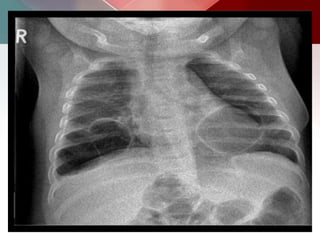

Plain radiograph

o Chest radiographs in type I and II CPAMs may demonstrate a

multicystic (air-filled) lesion.

o Large lesions may cause a mass effect with resultant mediastinal

shift, depression, and even inversion of the diaphragm.

o In the early neonatal period, the cysts may be completely or

partially fluid-filled, in which case the lesion may appear solid or

with air-fluid levels.

o Type III lesions appear solid.

CCAM type I

CT scan shows multiple large cysts (>2cm) involving the lower lobe of left lung. The cysts

are air-filled, expand the lower lobe, cause mediastinal shift and hypoplasia of right lung